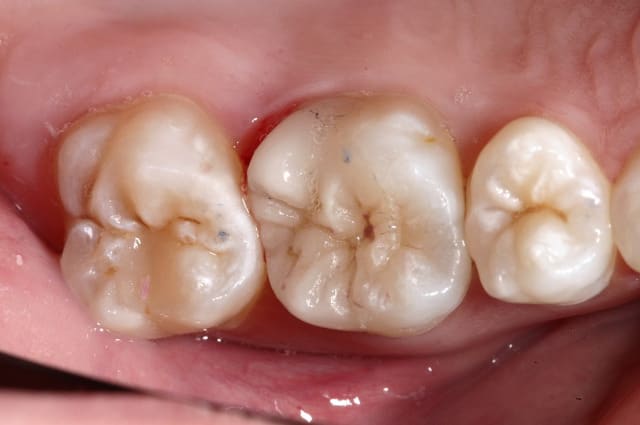

pour répondre à la question initiale du post, un cas de molaire dépulpée non couronnée.

Mise en place d'un cvimar (fuji II lc) en recouvrement de l'entrée canalaire puis onlay Empress collé.

Patiente de 21 ans.

Superbe travail de la céramique, Cingulum!

Désolé pour la qualité des photos, mais à cette époque je n'avais que ma vieille caméra endobuccale à fibre optique.